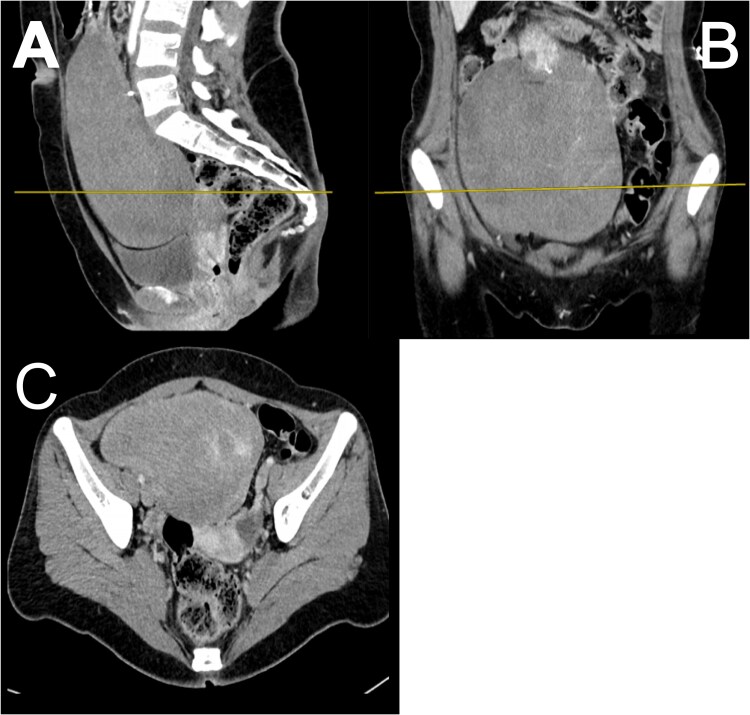

Large extraluminal gastrointestinal stromal tumours (GISTs) are rare, with varied presentations and patient profiles. This report discusses the case of a 22-year-old female presenting with a 4-month history of lower abdominal pain, weight loss, and recurrent urinary tract infections. Imaging revealed a large intra-abdominal mass (9.3 × 15.3 × 18.9 cm) originating from the stomach, extending into the pelvis, and compressing adjacent structures. During surgery, the mass was found to arise from the lesser curvature of the stomach and adhered to the transverse colon, with non-adherent extension into the pelvis and compression of adjacent organs. A gastric wedge resection and transverse colectomy were performed with aim of achieving a R0 resection. Histopathological analysis confirmed a GIST and positive resection margins. A plan for adjuvant imatinib was initiated in accordance with the European Society for Medical Oncology (ESMO) guidelines. This article details the challenges faced in the management of such a rare presentation and highlights similar reports.